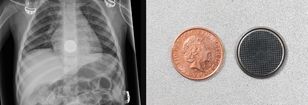

Prześwietlenie wykazało baterię w przełyku dziecka. Co robić, gdy dziecko połknie baterię?